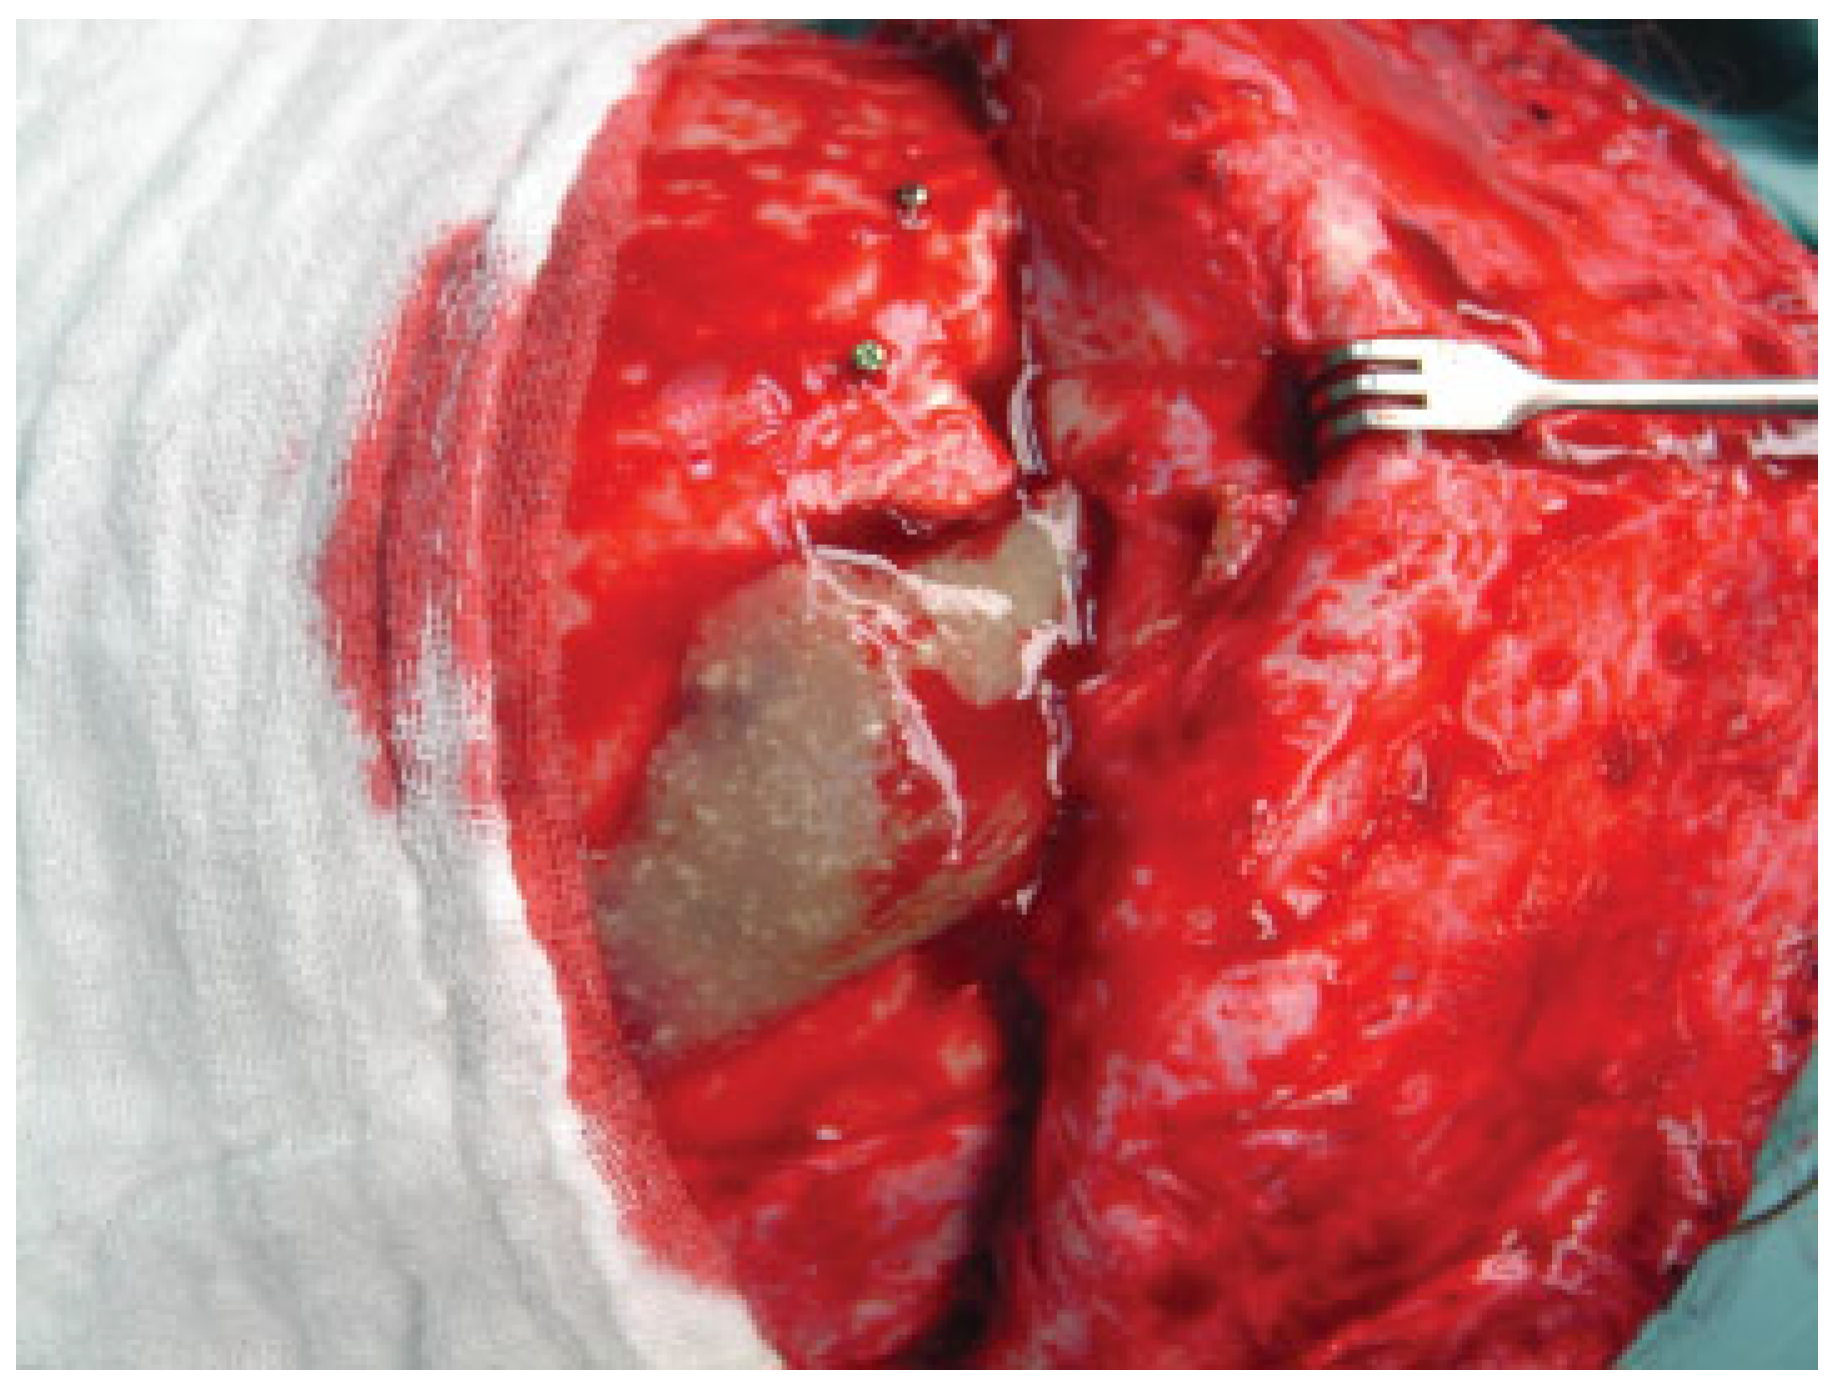

Anterior Table Fractures

Posterior Table Fractures

Nasofrontal Duct Injury